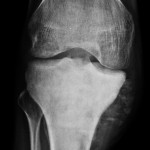

Image Challenge 11, #Oncology

24 year old man presented with pain and swelling in the knee for the past 3 months. Popular Answer may not imply right answer, follow our twitter handle for the right answer, www.twitter.com/drhiteshg Write your comments and explanations in the section below.